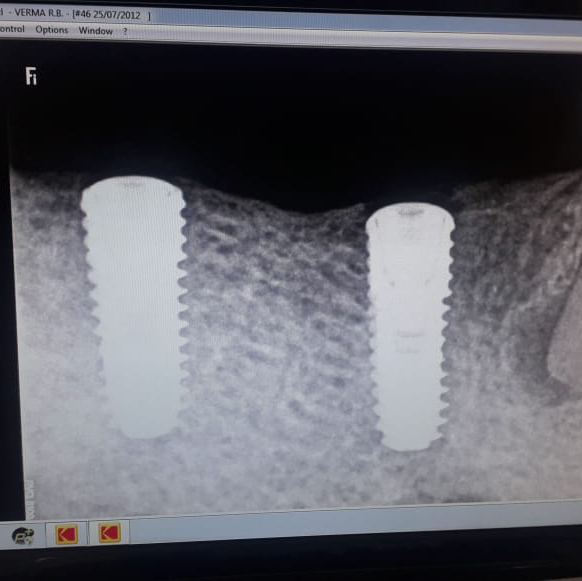

If you’ve ever wondered “Why are dental implants so expensive?” you’re not alone. At Align and Smile Dental Care, Sector 18 Noida, our patients often ask this question before deciding on tooth replacement options. Let’s break down what makes dental implants in Noida costlier than bridges or dentures—and why they’re still the best long-term investment for your smile. ⸻ 💎 1. High-Quality, Biocompatible Materials Dental implants are made from medical-grade titanium or zirconia, designed to fuse naturally with your jawbone through a process called osseointegration. These premium materials ensure strength, durability, and safety, which naturally increases the cost compared to traditional treatments. ⸻ ⚙️ 2. Advanced Technology and Precision Surgery At Align and Smile Dental Care, we use digital X-rays, 3D scans, and computer-guided implant surgery for precise placement. This level of planning minimizes complications and guarantees natural-looking results—adding to both quality and cost. ⸻ ⏱️ 3. Multi-Step, Customized Process An implant procedure involves several phases—diagnosis, surgery, healing, and final crown placement. Each step is customized to your jaw structure and bite, requiring multiple appointments and expert follow-up care. ⸻ 🩺 4. Specialist Expertise and Teamwork Implant dentistry demands skill and collaboration among surgeons, prosthodontists, and dental technicians. At our Noida dental clinic, every case is planned meticulously by experienced implant specialists, ensuring safety and long-term success. ⸻ 💰 5. Long-Term Value, Not Just Cost While the upfront price may be higher, dental implants can last for decades with proper care—unlike bridges or dentures that need frequent replacement. This makes them a cost-effective, permanent solution that restores both function and confidence. ⸻ 🌟 Why Choose Align and Smile Dental Care, Sector 18 Noida? • Experienced implant specialists • Latest laser and digital dentistry technology • Hygienic, sterilized environment • Transparent pricing and treatment planning • Convenient location near Sector 18 Metro Station, Noida ⸻ 🦷 Final Takeaway Dental implants are an investment in your oral health, comfort, and confidence. At Align and Smile Dental Care, Noida, we combine advanced technology with compassionate care to make your implant journey smooth and rewarding. ⸻ 📞 Book Your Consultation Today Looking for affordable dental implants in Noida or want to know if you’re a good candidate? Visit Align and Smile Dental Care, Sector 18 Noida, or call us to schedule your consultation today! 🌟 Our Key Services • Dental Implants in Noida – Permanent tooth replacement with high-quality titanium or zirconia implants. • Invisalign & Braces – Clear aligners, ceramic, and metal braces for perfectly aligned teeth. • Root Canal Treatment – Painless, precise RCT using modern rotary systems. • Cosmetic Dentistry – Teeth whitening, veneers, and smile makeovers for a confident smile. • Pediatric Dentistry – Gentle dental care for kids in a comfortable environment. • Gum Treatment – Scaling, polishing, and laser gum therapy for healthy gums. • Crowns, Bridges & Dentures – Natural-looking, durable restorations. • Preventive Check-ups – Regular cleanings and oral health maintenance.